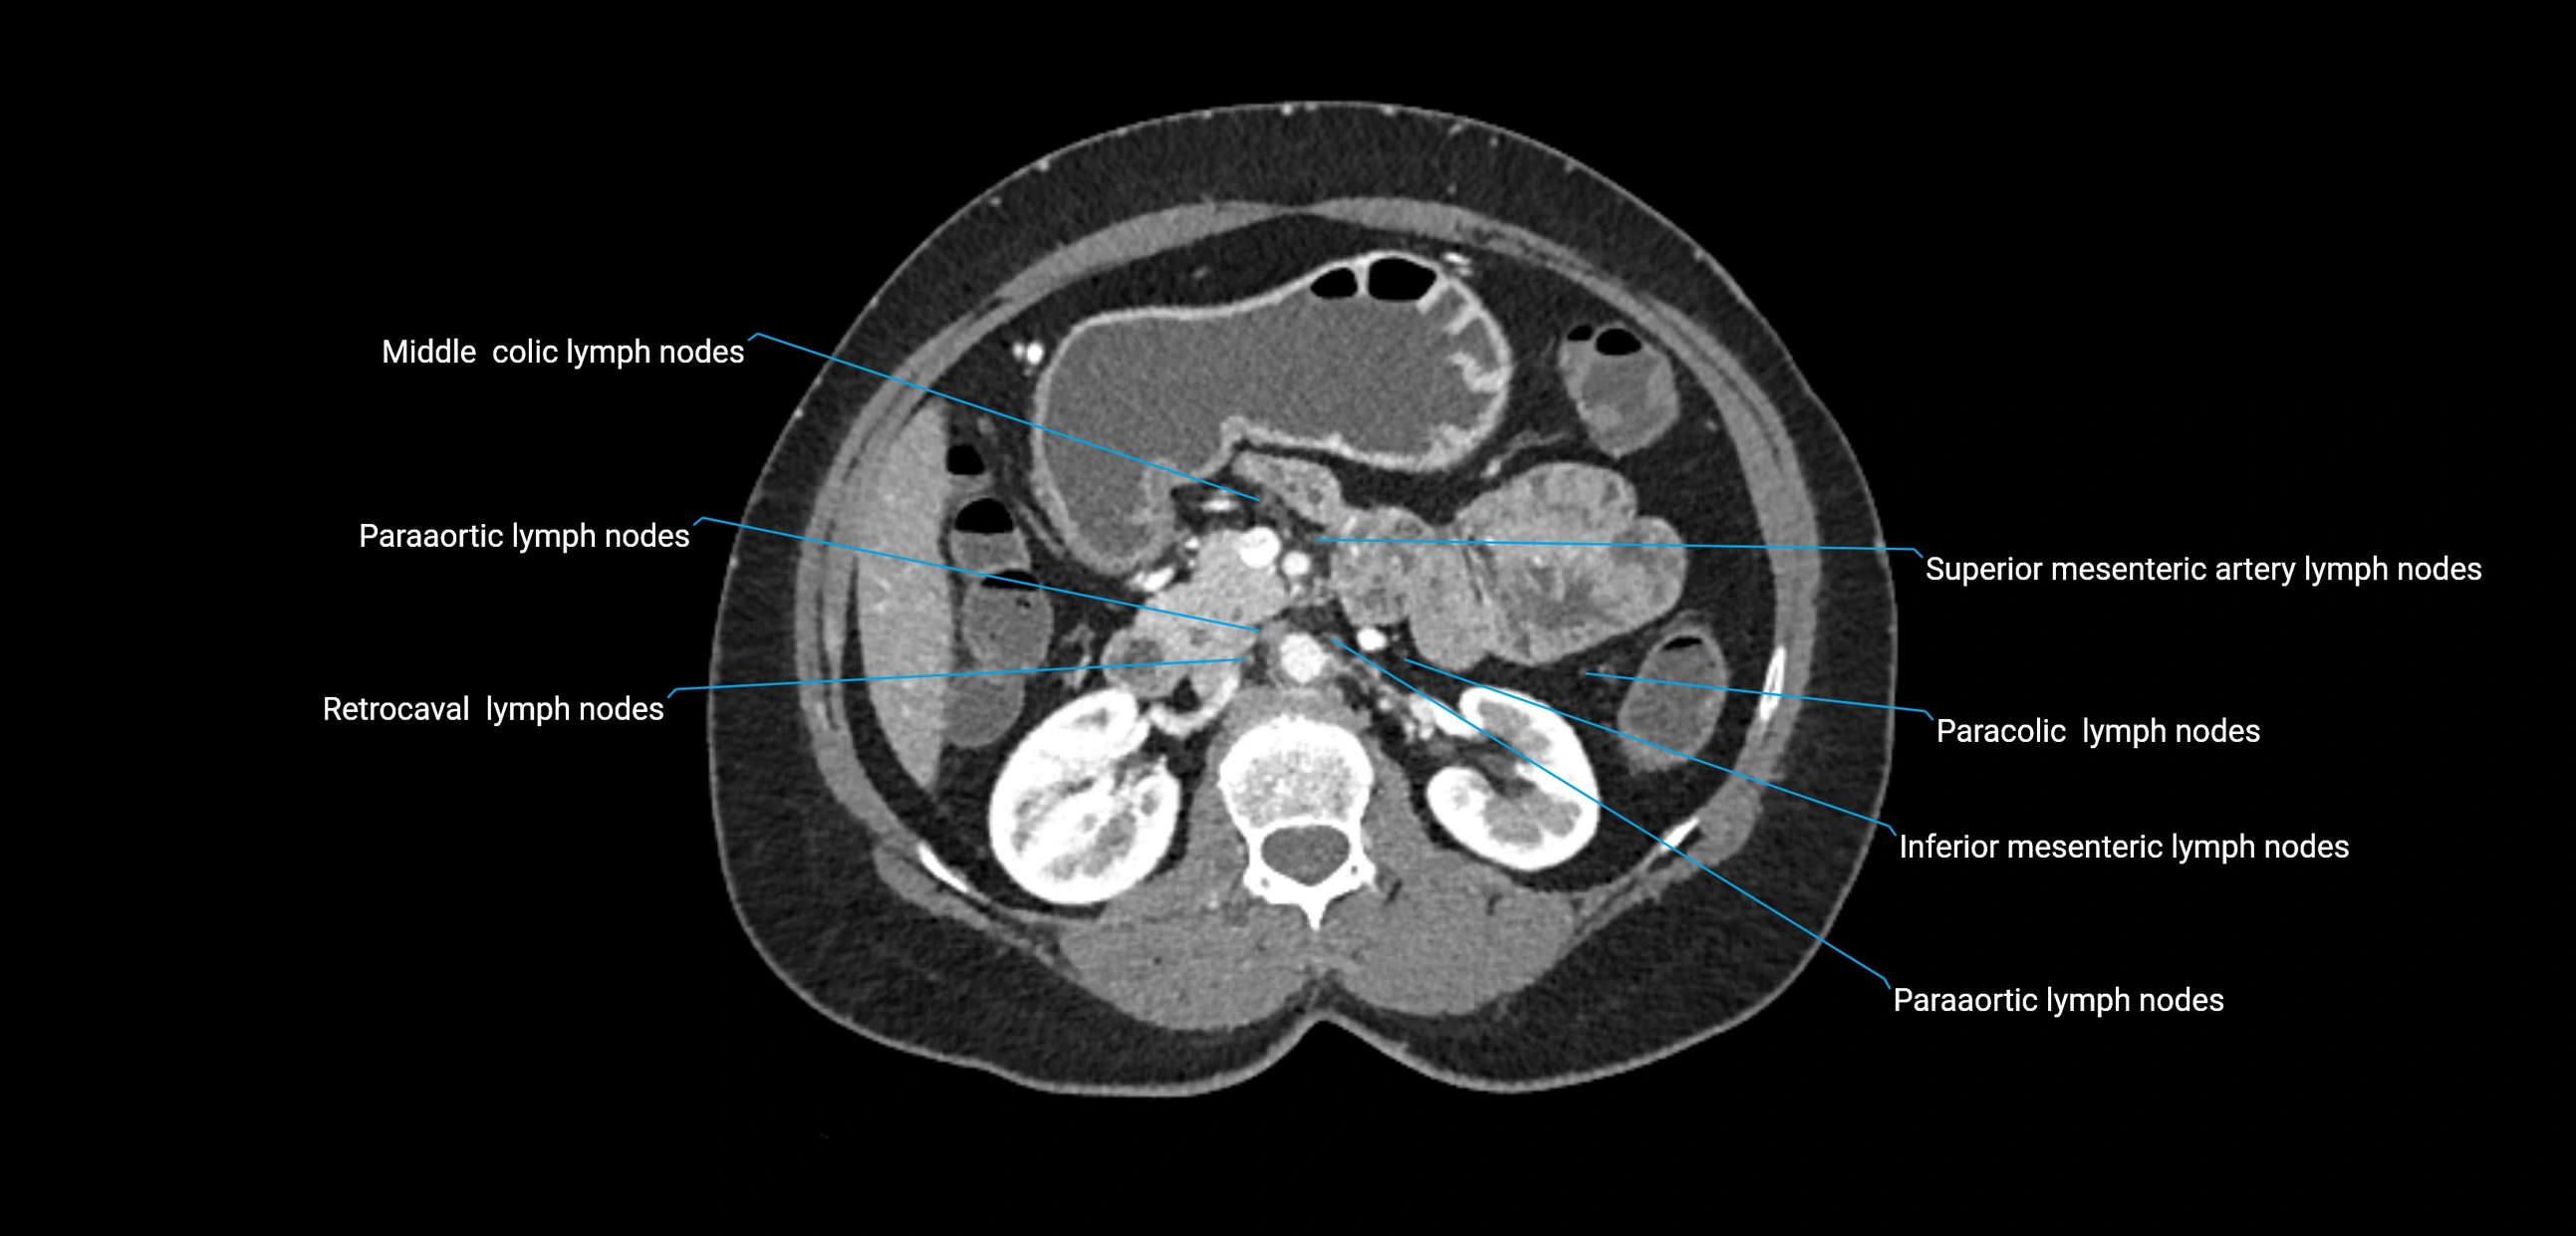

CT image

image